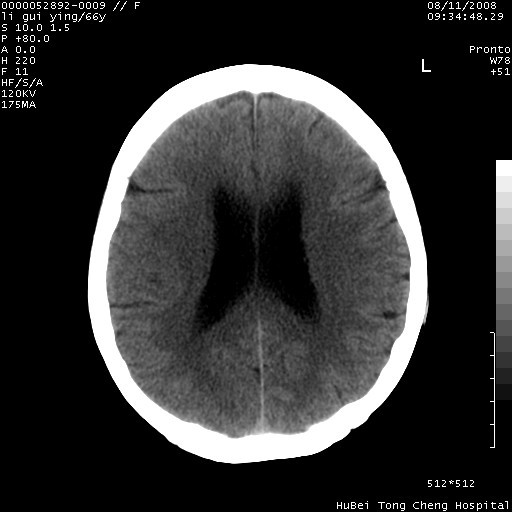

以下是引用yangyudong333在2008-8-12 12:22:00的发言:[br]1.病灶呈圆形[br]2.周围无水肿带[br]3.密度不均匀,内有点状钙化[br]4.无占位效应[br] 考虑良性占位性病变,血管瘤可能性大